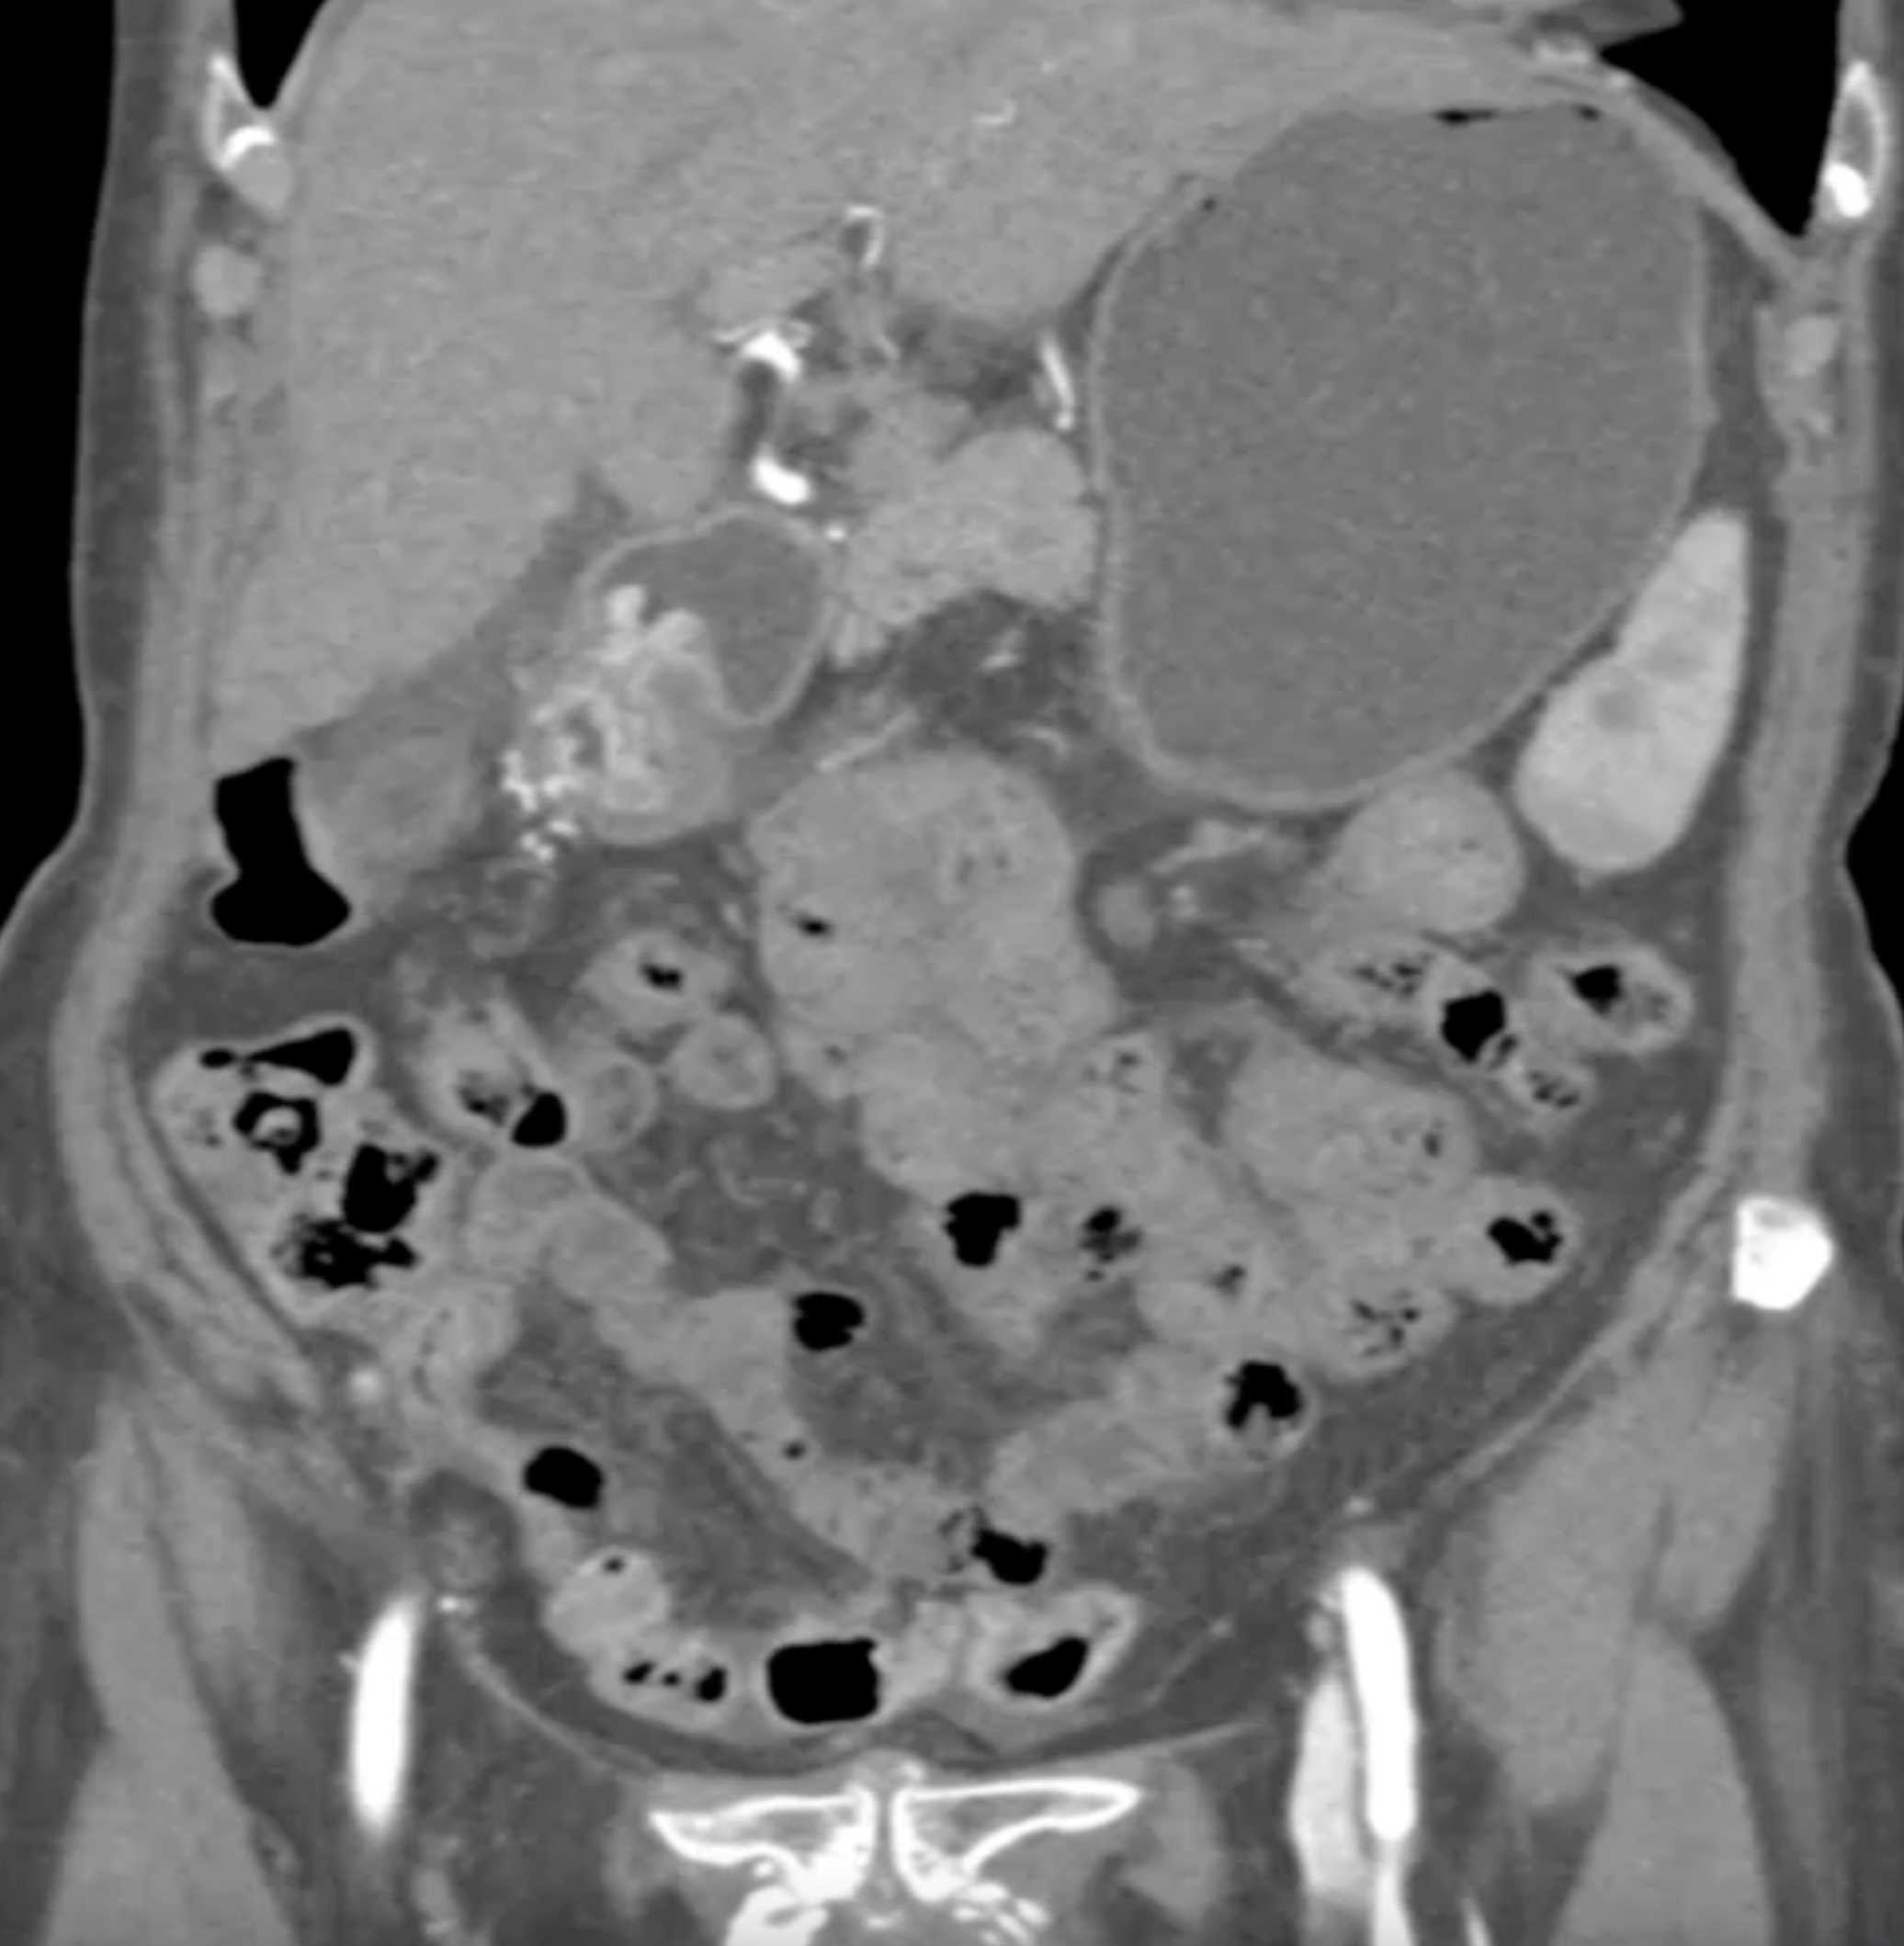

Watermelon Stomach (Gastric Antral Vascular Ectasis)